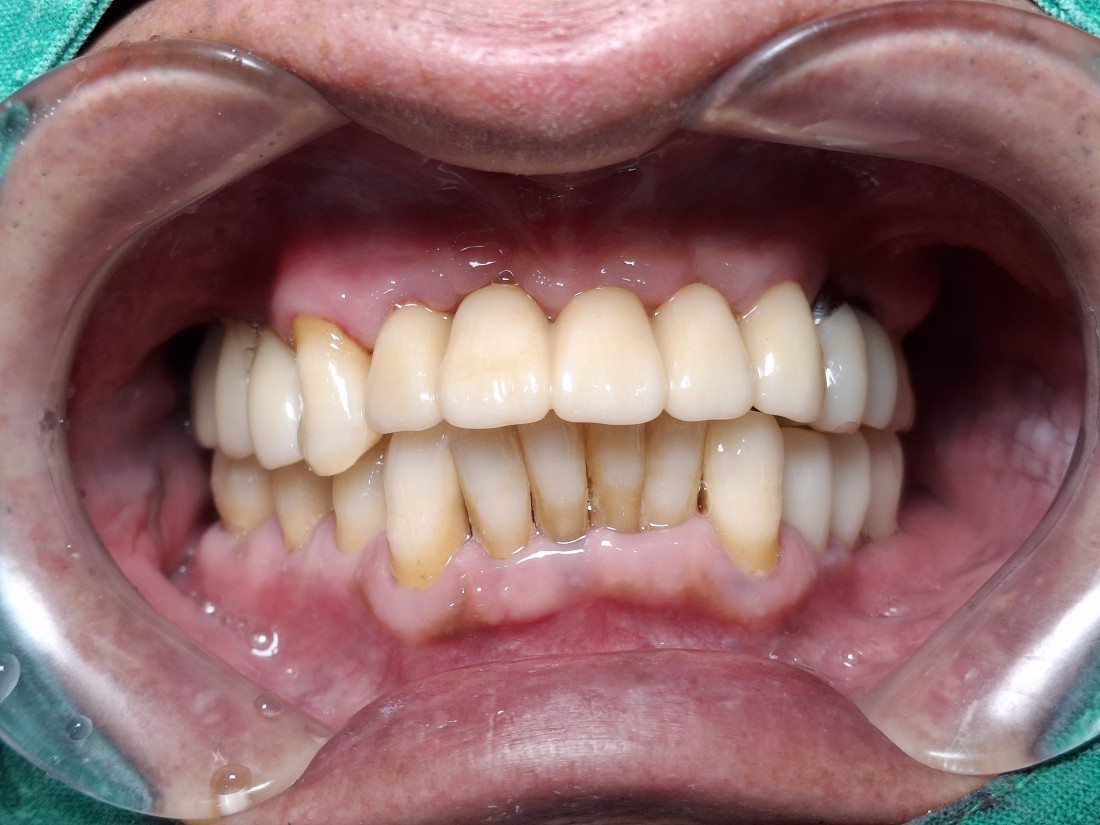

핑크포세린을 이용하여

자연스러운 아름다움을 만드는

광주 앞니 임플란트 치과에서

또한 자체 치아기공소를 운영하여

앞니임플란트를 광주 앞니임플란트 치과 중

어느 치과보다 더 자연스럽고 아름답게

완성할 수 있는 자신이 있습니다.

광주 앞니임플란트 치과에서

자연치아만큼 아름다운 앞니임플란트를

완성할 수 있는 비결에는

'핑크 포세린'을 이용하여

잇몸을 제작하기 때문에

더욱 자연스러운 아름다운 앞니를

연출할 수 있기 때문입니다.